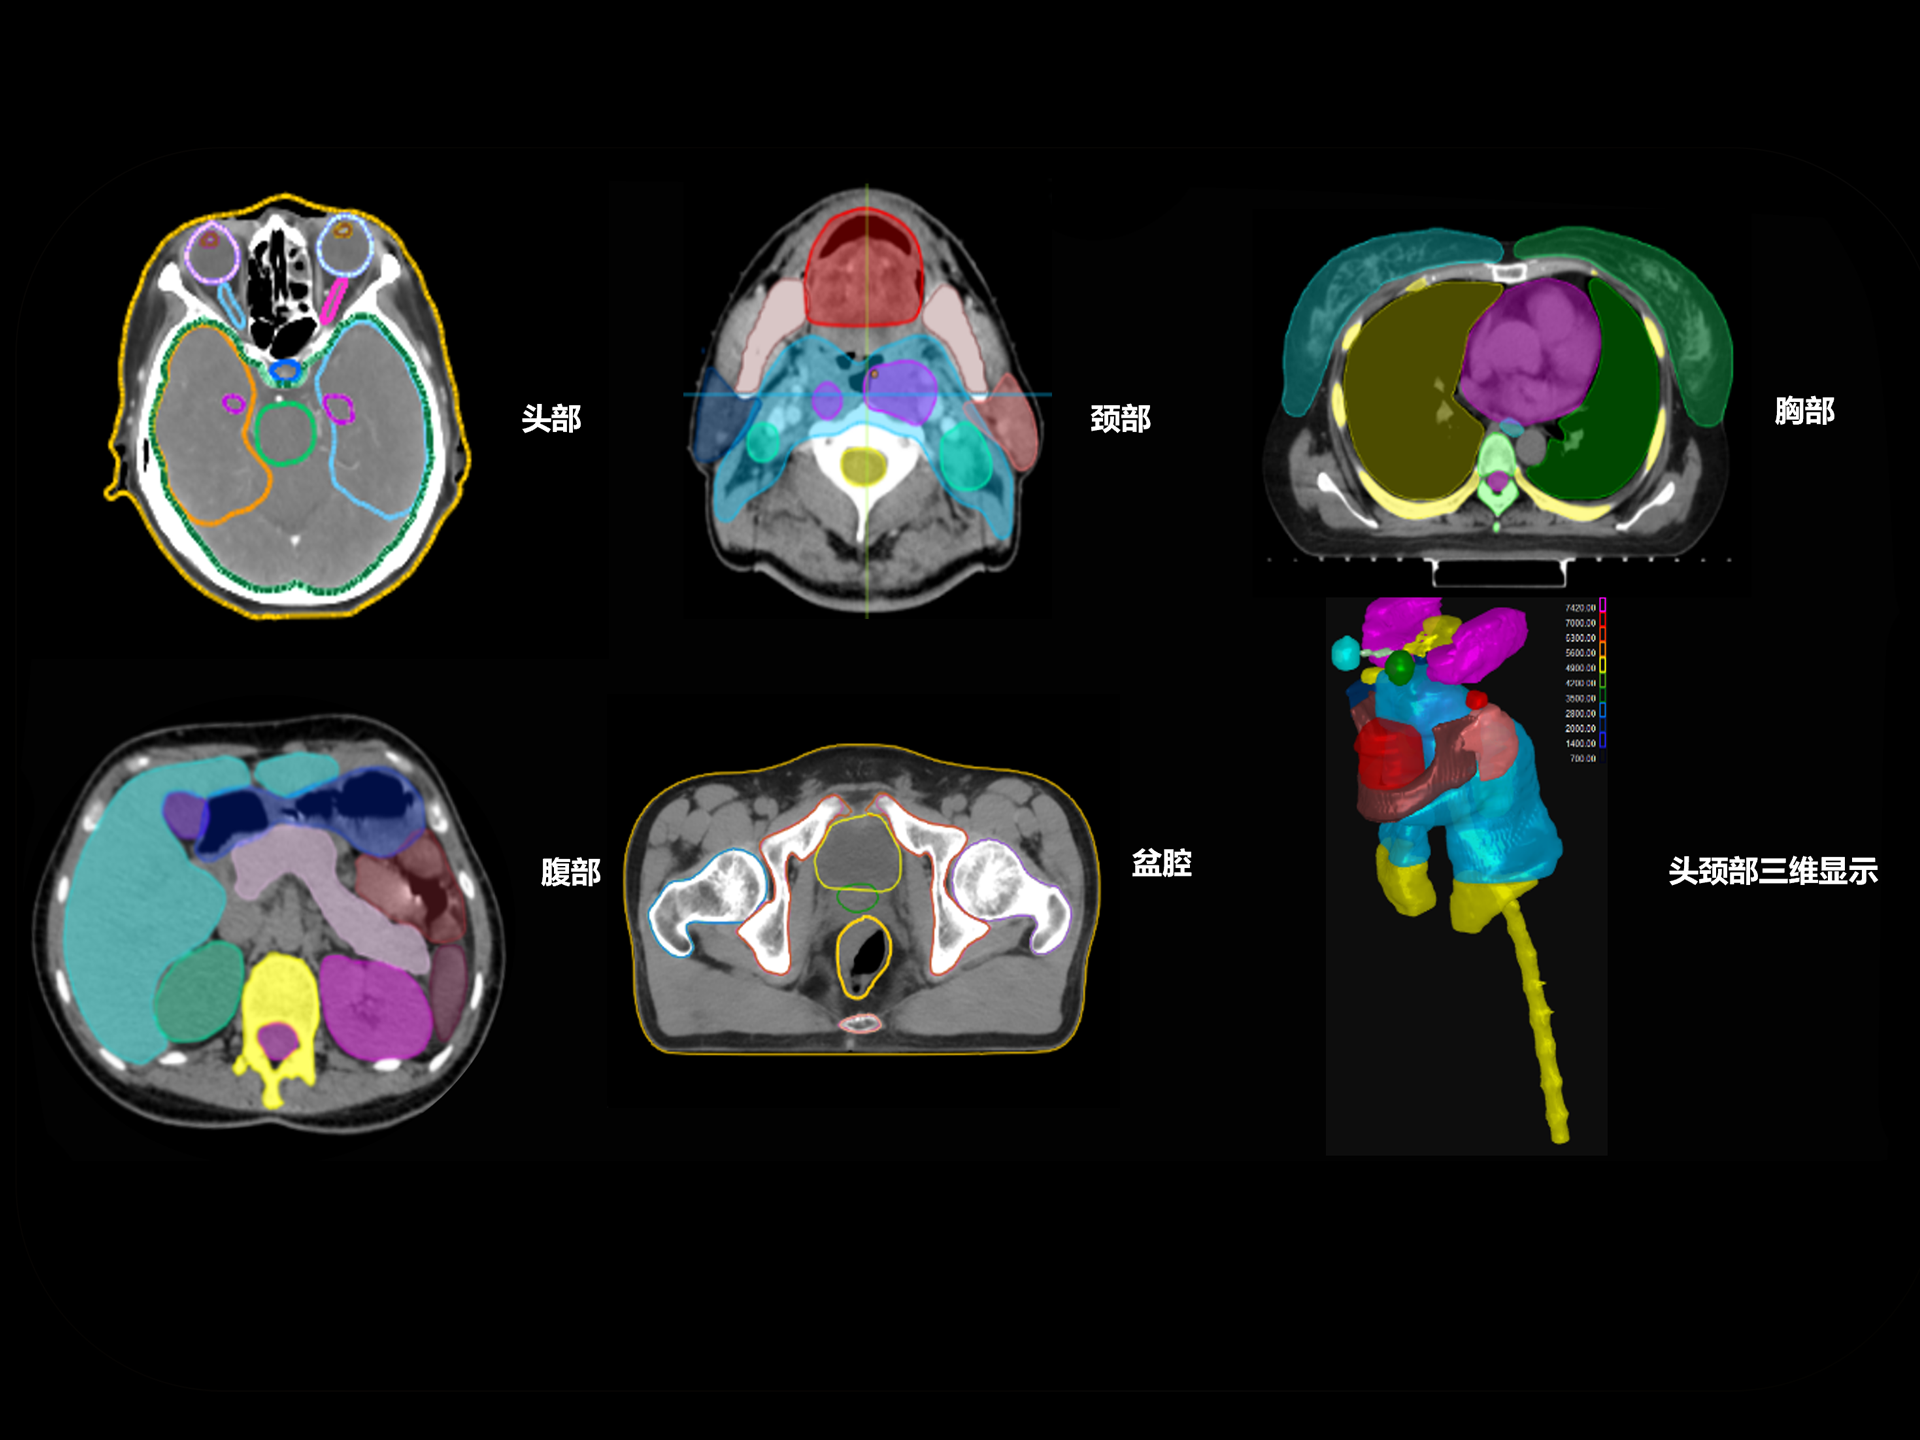

支持CT、MR、PET多模态影像及全身100+器官勾画模型,准确度高、分割速度快、重现性好,提高临床勾画效率与一致性。

亚秒级自动勾画